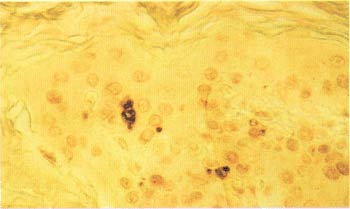

图4 DeadEnd™比色法细胞凋亡检测系统标记鼠脑模型中轴突横切术诱导的细胞死亡的外侧膝状体核(LGN)的细胞核(11,12)。

低聚甲醛/戊二醛混合鼠脑的振动切片机切片(50μm)显示脑轴索化一侧的LGN细胞被深染,而同一切片中的另一侧细胞则未被染色。(插入图片所示)“洗衣板”效果是振动切片机切片过程中的人为因素造成的。

接上一页)的神经细胞过量死亡。(12,13)在LGN中的神经元被病灶轴索化,这个过程导致细胞在病灶诱导后精确的时间萎缩或死亡。这种轴索显微外科术诱导的细胞死亡在病灶产生3天内,LGN同侧只有5%的神经元死亡,而病灶产生3-7天内,大量神经元死亡发生了。大约有2/3的背部同侧的LGN在此期间经历细胞凋亡(12)。图4中,DeadEnd™比色法凋亡检测系统直接标记在LGN同侧到病灶的诸多细胞核,而LGN异侧到病灶的细胞则未被标记。结果清晰地显示了此系统在轴突横切术诱导的神经元死亡模型中标记凋亡细胞核中的效用。